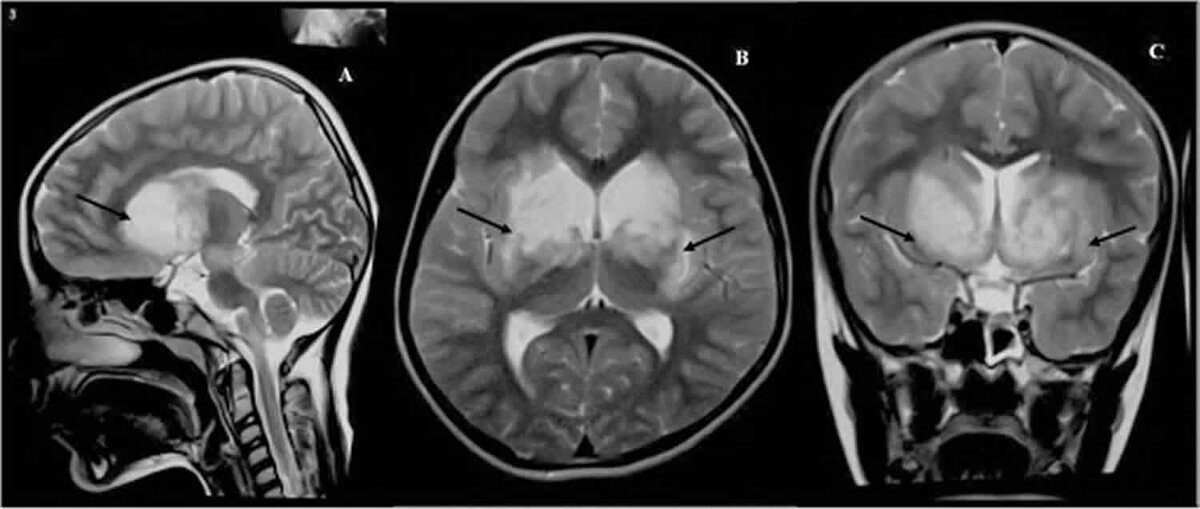

Врач может использовать МРТ головного мозга, чтобы определить степень повреждения височной доли человека. Он также может назначить анализ крови и спинномозговой жидкости для проверки на наличие инфекции головного мозга, а также ЭЭГ для оценки наличия судорог.